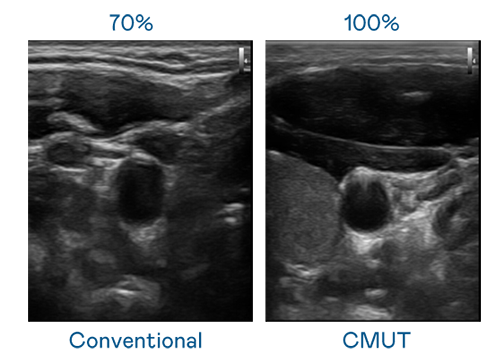

CMUT 技术是一种用电容式微机电元件来产生超音波讯号的技术。与传统 PZT 压电式技术相比,CMUT 频宽增加 30%,更宽频的超音波讯号让影像解析度大幅提升,是实现高影像品质医疗超音波扫描、促进精准医疗发展的关键技术。

大频宽带来超清晰影像

超音波影像的解析度高低,首先取决于探头能发出的讯号频宽。⽜⼋体育 CMUT 可提供高清晰的超音波讯号,提供高频宽、高灵敏度、影像纹理细节更高的超音波影像,协助医护人员缩短影像判读时间及利用精准的医疗影像进行诊断。